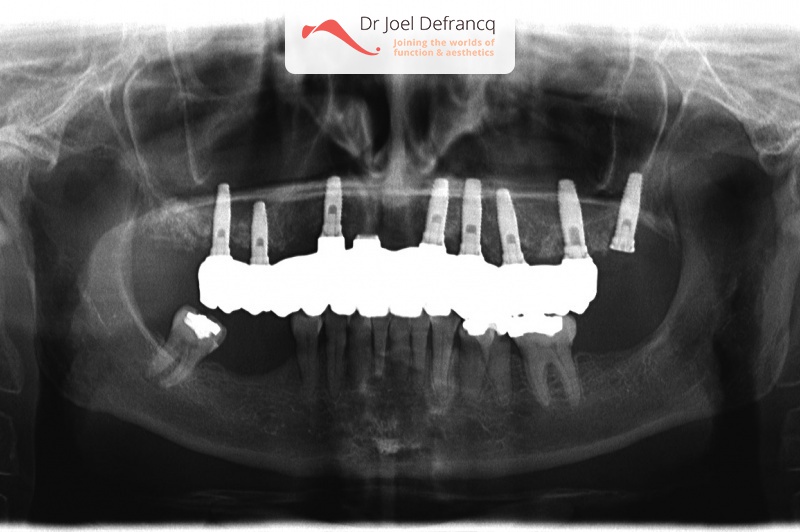

Axelle: new teeth in a week - implants.

Behandeling tandheelkundige implantaten

- Vaste tanden op implantaten (bovenkaak)